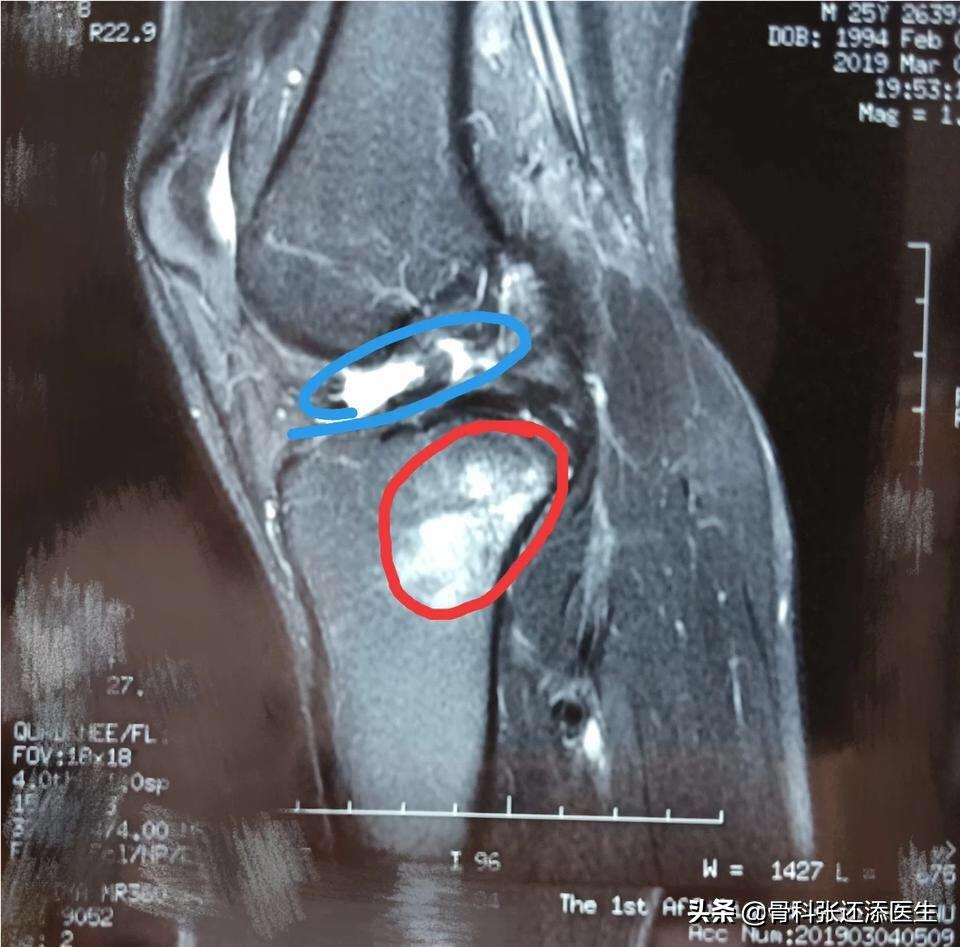

我有一个病友,是打篮球的小伙子,当年在赛场感觉膝盖咔嚓响了一下,立刻疼痛不能动弹,后来拖成了陈旧性损伤。他来门诊,片子显示,前交叉韧带部分撕裂(蓝色),胫骨后方多处骨髓水肿(红色)。

膝盖走路咯噔响还疼是什么原因,膝盖弯曲膝盖响是什么原因

膝关节前交叉韧带(ACL)陈旧性损伤,属于当初发生撕裂损伤没有好好治疗,残存撕裂部分,也会引发膝关节的弹响,反复出现疼痛,就需要到医院尽早治疗。可以行关节镜手术,做ACL重建,避免伤害愈来愈扩大。